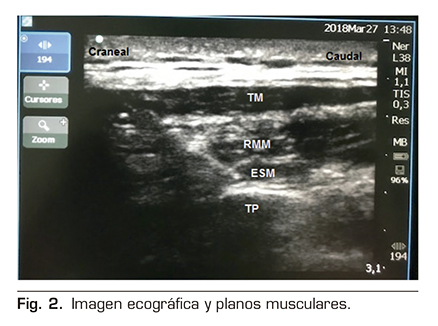

Figura 1

Figura 2

Figura 3